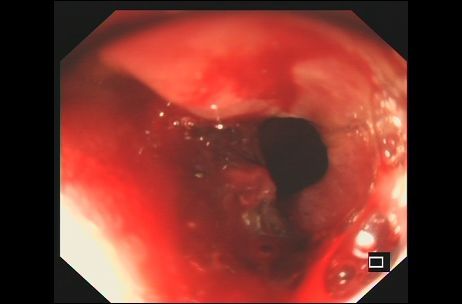

胃肠镜提示:肿瘤已侵入十二指肠腔内并导致肠腔狭窄。

湖南临湘的李先生今年51岁,一年前曾因升结肠癌做了右半结肠癌根治手术,并接受为期半年的化疗。可在一次常规复查中发现,其右肾前方新发一个病灶,高度怀疑为局部复发。虽然更改了多次化疗方案,但似乎每种药物对肿瘤都没太大作用,肿瘤还在不断增大,并累及十二指肠。